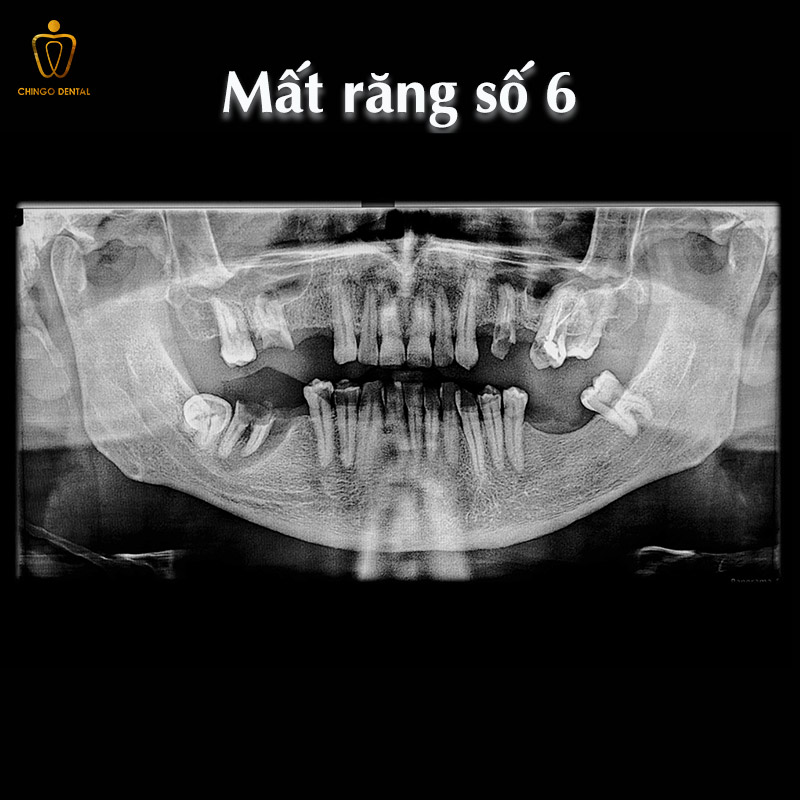

Mất răng số 6 có nguy hiểm không?

Nhiều người chủ quan cho rằng mất một chiếc răng hàm phía trong sẽ không ảnh hưởng đến thẩm mỹ nên thường trì hoãn việc điều trị. Tuy nhiên, việc mất răng số 6 mang lại những hệ lụy cực kỳ nghiêm trọng.

Khi có khoảng trống, các răng lân cận (răng số 5 và số 7) sẽ có xu hướng đổ nghiêng về phía khoảng mất răng. Răng đối diện ở hàm khác sẽ trồi xuống hoặc trồi lên, gây ra sự sai lệch khớp cắn toàn diện.

Hơn nữa, mất răng số 6 hàm dưới có sao không là băn khoăn của nhiều bệnh nhân. Câu trả lời là có, vì nó dẫn đến tình trạng tiêu xương hàm tại vị trí mất răng. Theo thời gian, điều này không chỉ gây khó khăn cho việc phục hình sau này mà còn làm thay đổi cấu trúc cơ mặt, gây ra tình trạng lão hóa sớm.

Hoàn toàn có thể nhổ được, nhưng đây là một thủ thuật cần sự cẩn trọng cao. Vì răng số 6 có hệ thống chân răng sâu và phức tạp. Bác sĩ cần tiến hành chụp X-quang để xác định chính xác vị trí chân răng và các dây thần kinh xung quanh.